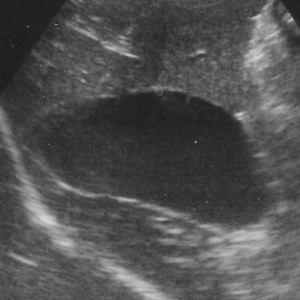

左下の写真が胆嚢粘液嚢腫の胆嚢の超音波検査のイメージです。本来は、画像上で真っ黒く抜けている円形の胆嚢の断面像に「キウイフルーツ」の切り口のように見えるようなパターンを生じるのが典型的ですが、その他に胆泥症との区別が難しいものなど、幾つかのバリエーションに富む異常を呈します。比較のために正常な胆嚢を右の写真を右写真に示します。